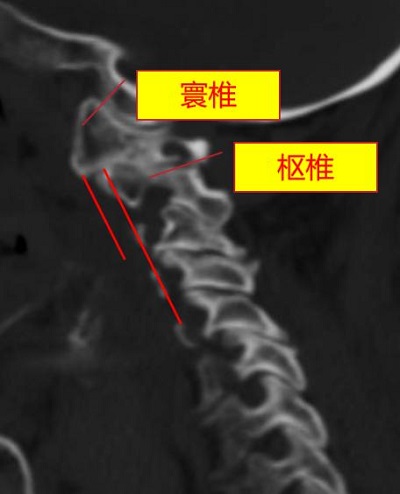

術前,頸椎CT顯示寰樞椎脫位(正常為寰椎、樞椎在同一水平線)。重慶市人民醫院(重慶大學附屬人民醫院)供圖